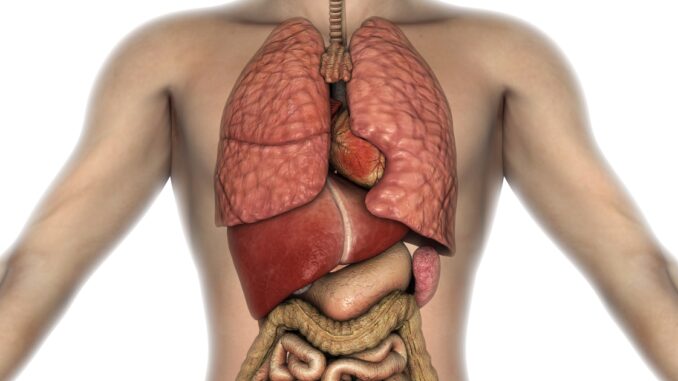

Lidské tělo je fascinující, složitý a dokonale fungující celek, ve kterém má každý orgán svou přesně danou roli. Každý den v našem organismu probíhají tisíce procesů, o nichž většinou ani netušíme, že se dějí. Srdce pumpuje krev, plíce zpracovávají kyslík, mozek vysílá signály, které se pohybují rychlostí blesku. Přestože své tělo používáme neustále, často nás překvapí, jak málo o něm víme. Víte například, který orgán je skutečně největší? Nebo kolikrát se průměrný člověk nadechne během jediného dne?

Lidské tělo je dokonalý stroj